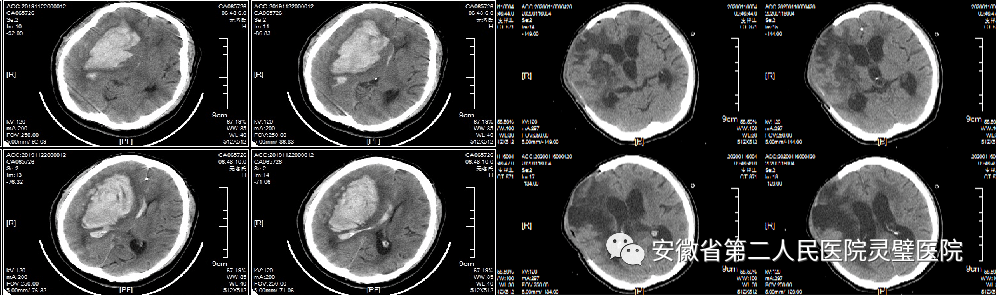

脑出血是临床常见神经重症,原发性高血压是最常见原因之一,根据病人的不同特点,我科形成了从保守治疗、微创治疗到去大骨瓣减压等系列个性化特色技术,临床救治水平达到国内先进水平。

经额穿刺血肿引流术

经颞小骨窗神经内镜下血肿清除术

去大骨瓣减压术+脑内血肿清除术